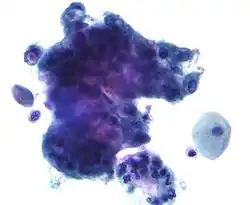

HSIL: high-grade squamous intraepithelial lesion

High-grade squamous intraepithelial lesion (HSIL or HGSIL) indicates moderate or severe cervical intraepithelial neoplasia or carcinoma in situ. It is usually diagnosed following a Pap test. In some cases, these lesions can lead to invasive cervical cancer, if not followed appropriately.

HSIL does not mean that cancer is present. Of all women with HSIL results, 2%[8] or less[9] have invasive cervical cancer at that time; however, about 20% would progress to having invasive cervical cancer without treatment.[10] To combat this progression, HSIL is usually followed by an immediate colposcopy with biopsy to sample or remove the dysplastic tissue. This tissue is sent for pathology testing to assign a histologic classification that is more definitive than a Pap smear result (which is a cytologic finding). HSIL generally corresponds to the histological classification of CIN 2 or 3.

HSIL treatment involves the removal or destruction of the affected cells, usually by LEEP. Other methods include cryotherapy, cautery, or laser ablation, but none are performed on pregnant women for fear of disrupting the pregnancy.[11] Any of these procedures is 85% likely to cure the problem.